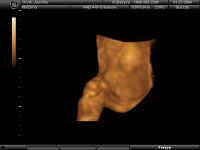

Sneak Preview of Baby Orvik (due March 27 2004)

Although he/she is not due for another two months, 3D Ultrasound technology allowed us to get a glimpse of Baby O. These are a little tough to interpret, so here are some pointers: these are all face shots, with baby facing the left side of your screen. You are seeing a profile or 3/4 profile, and in pictures 3-5, there is a hand in front of the face -- looks like we have a thumb sucker. Pictures 1 and 2 are the least complete, and picture 5 is probably the best image, but you'll have to use your imagination in all of them, fill in the blanks, and don't worry if anything looks odd -- baby is fine.